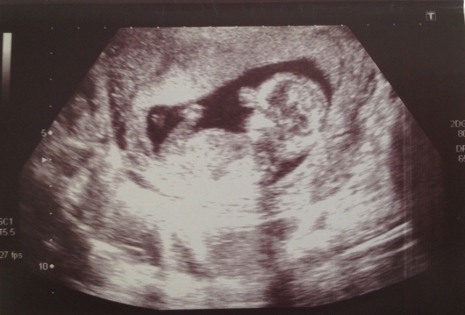

„Milyen nagy! Ez volt az első gondolatom, mikor megláttam a második ultrahangképet – írta blogján Raquel. – Kétségtelenül az egyik legizgalmasabb pillanat volt az életemben.”